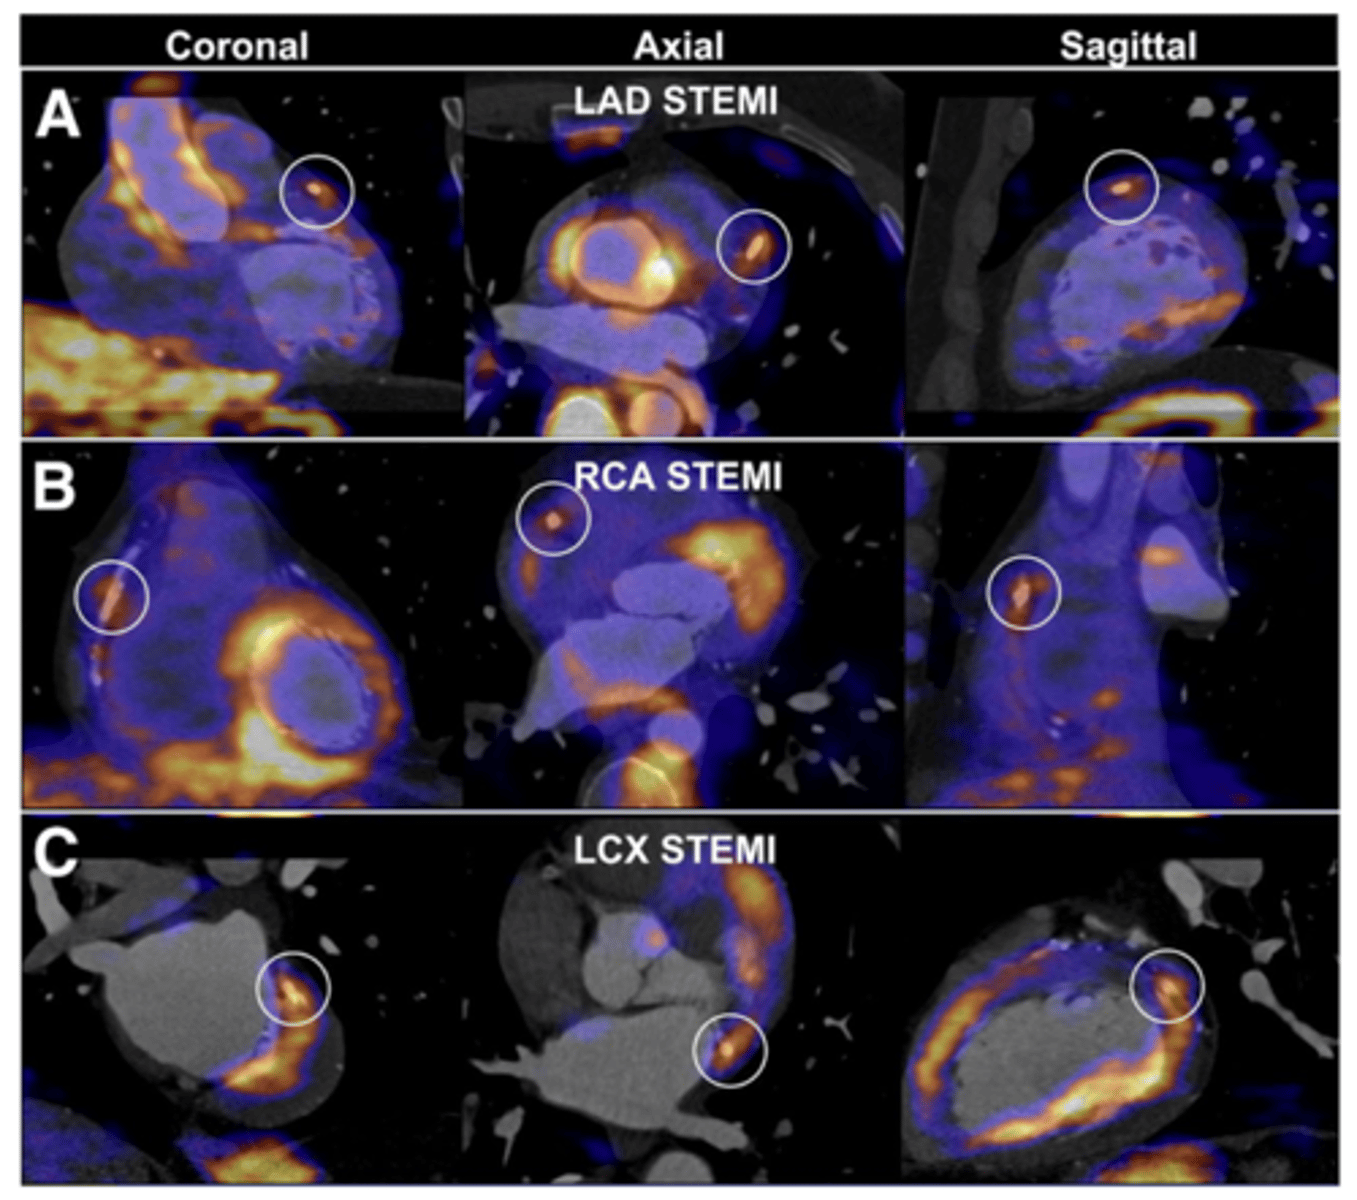

What imaging/tests can be used to eval coronary artery dz? What does each test look for?

◼ A thallium stress test evaluates the musculature of the

left ventricle during rest and under stress.

◼ The echocardiogram looks for regional wall motion abnormalities – can also be done with stress

◼ Coronary angiography (cardiac cath) is the best study to visualize the coronary arteries but is expensive, invasive and involves a high dose of radiation.

<p>◼ A thallium stress test evaluates the musculature of the</p><p>left ventricle during rest and under stress.</p><p>◼ The echocardiogram looks for regional wall motion abnormalities – can also be done with stress</p><p>◼ Coronary angiography (cardiac cath) is the best study to visualize the coronary arteries but is expensive, invasive and involves a high dose of radiation.</p>

What would an abnormal thallium scan look like?

#1 test for evaluating stress -->.R image indicates void of uptake and dec blood supply

<p>#1 test for evaluating stress --&gt;.R image indicates void of uptake and dec blood supply</p>